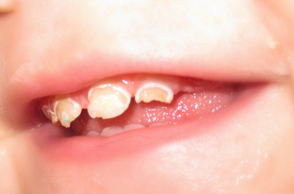

Oštećenja u gleđi zuba u razvoju(dok još nije iznikao) mogu da izazovu i lokalni uzroci. To su najšešće utisnuće mlečnog zuba ili infekcija u kosti oko obolelog mlečnog zuba. Tada se razvojno oštećenje gleđi javlja na stalnom zubu. (Slika 3.)

Stalni sekutići(desno) je povređen od strane mlečnog zuba u toku razvoja tako da je izostala izgradnja gleđi